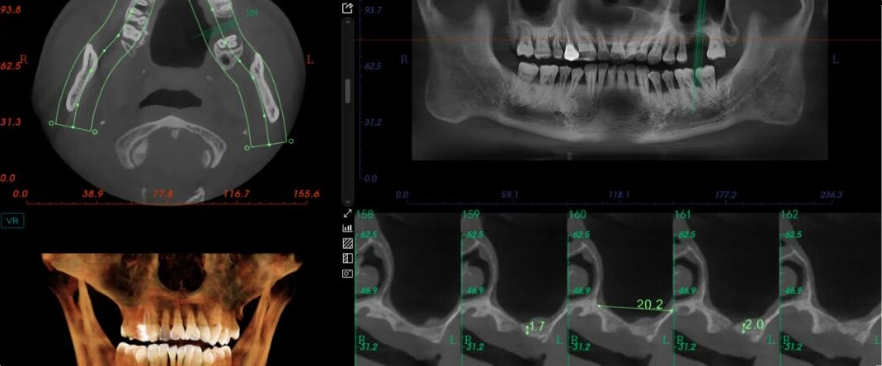

种植术前需要完善的检查和诊断,全面了解患者情况,并且详细的判断和分析,才能指导下一步修复方案的设计。

x光片检查,检查口腔中要修复的基牙是否有病变,是否可以进行下一步操作。